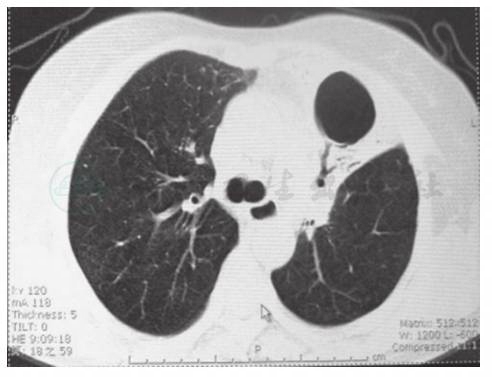

胸部CT可见左肺上叶大片状高密度渗出实变影,左肺下叶及右肺多发散在小片状高密度渗出灶(图1);随着病情发展,可见左上肺实变阴影内囊泡影(图2)。

图2 胸部CT表现(2010-09)